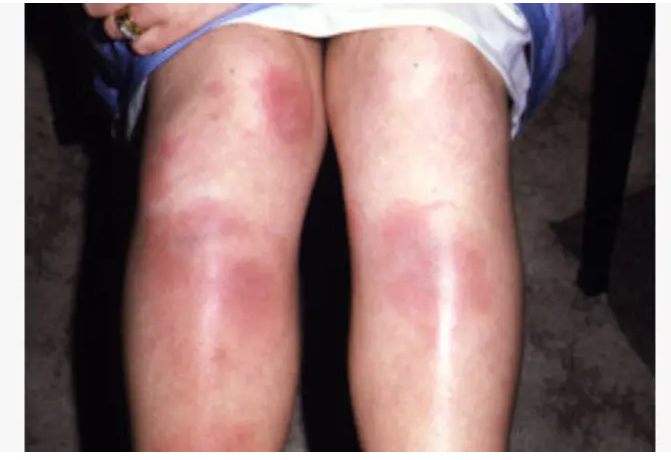

Valley fever is common name of deadly fungus Coccidioides immitis or Coccidioides posadasii.

Can affect any body organ.